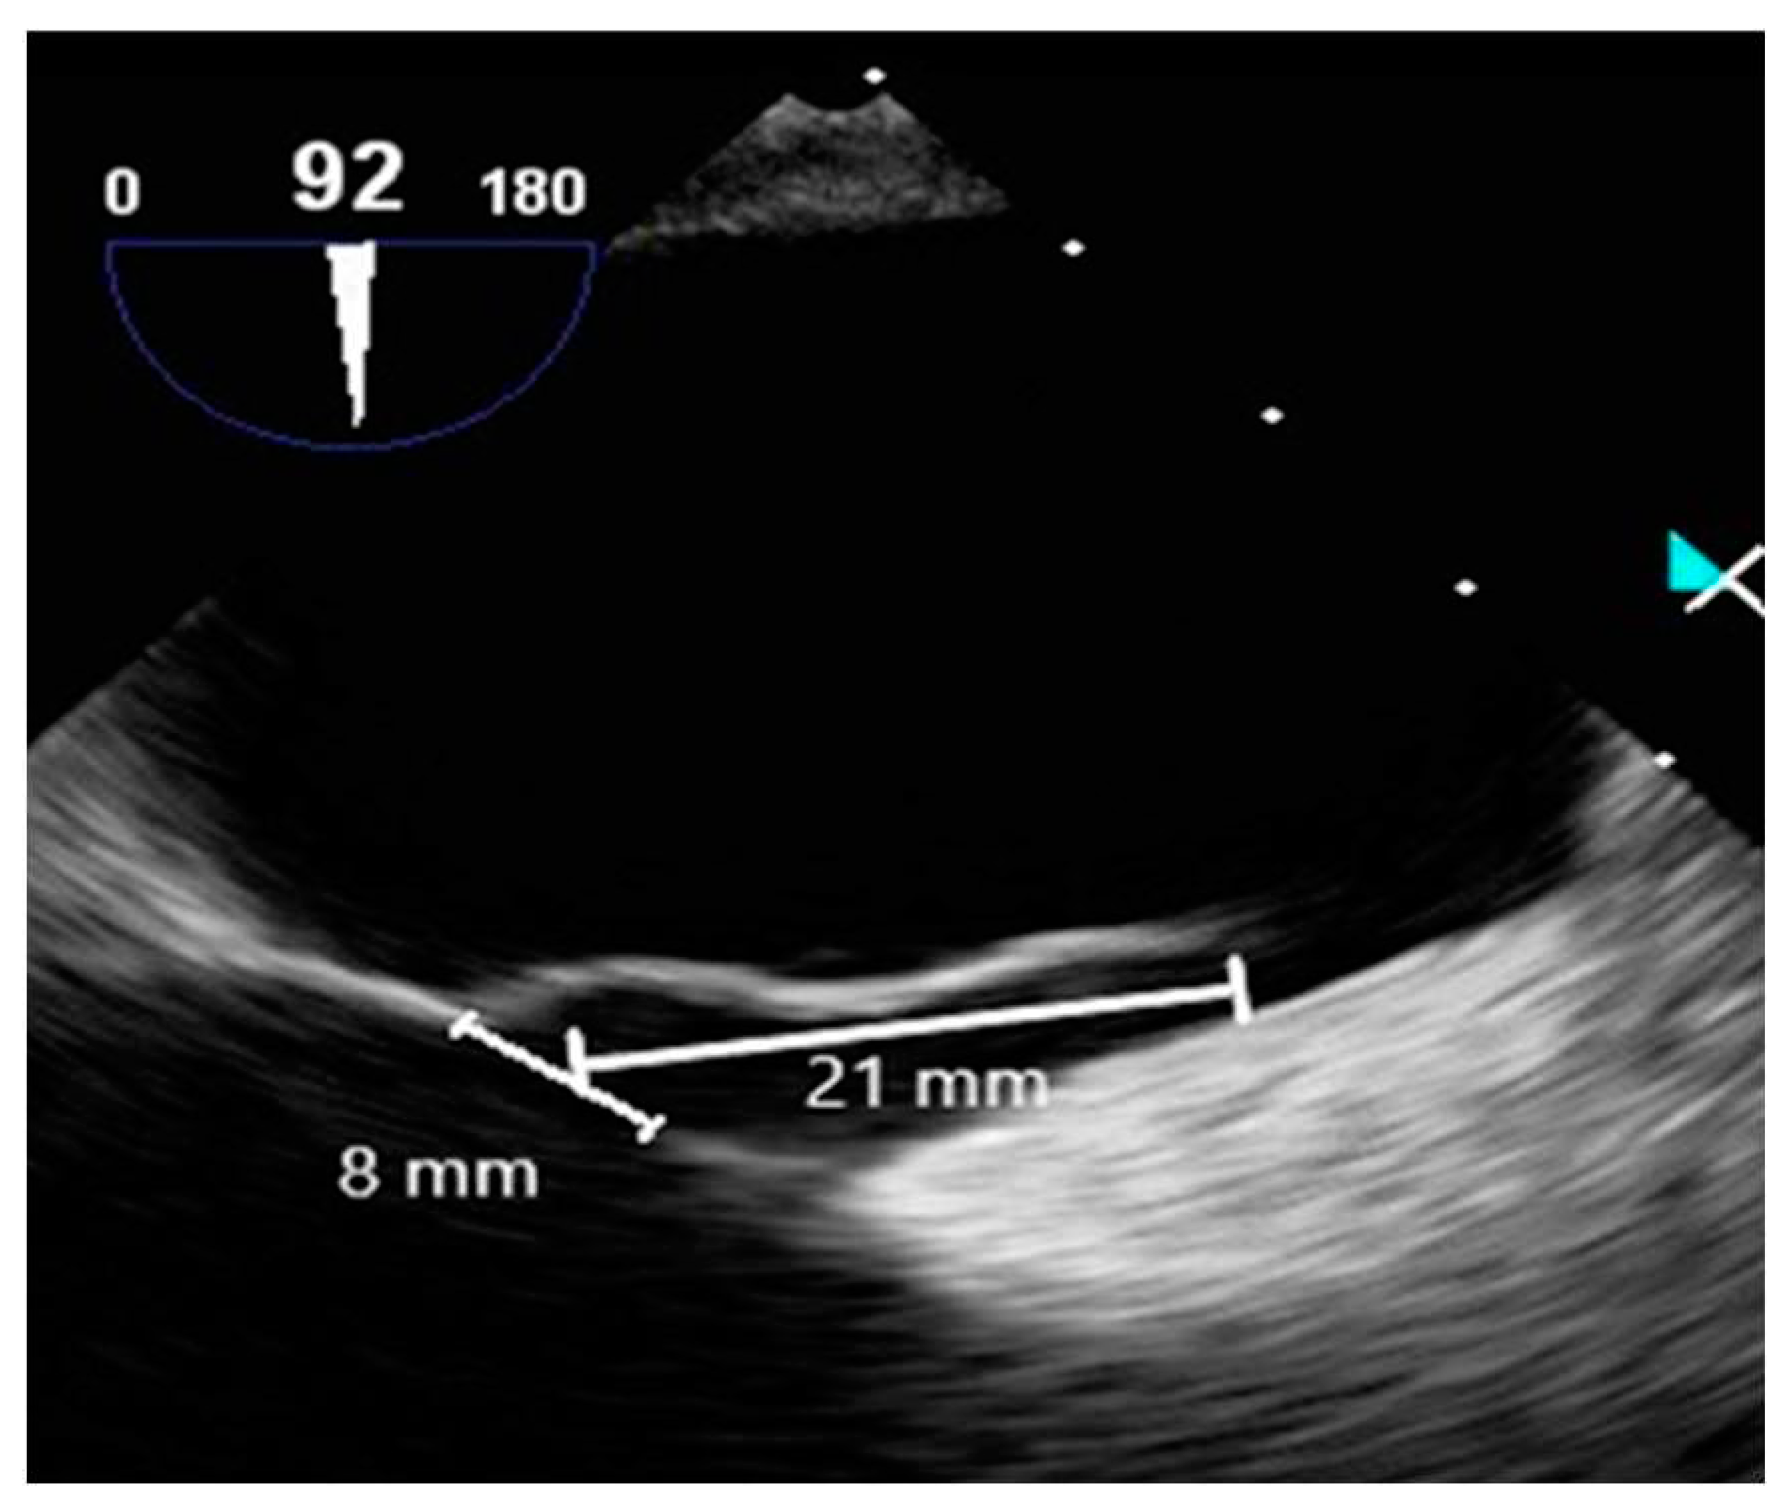

Contrast-enhanced TEE assessed the morphology of PFO and timing of RLS. TEE employed an ultrasound machine (Affiniti 70C, Philips, USA) and a probe (X7-2t, Philips, USA), which were operated by a cardiologist. A manufactured bubble contrast agent enhanced the images. TEE revealed a PFO diameter of approximately 8 mm, a tunnel length of approximately 21 mm, and a hypermobile interatrial septum (Figure 6).

Figure 6. TEE view of measured PFO diameter and tunnel length.

The evaluation of the PFO through TEE revealed a size of approximately 8 mm, with the tunnel spanning about 21 mm. Real-time imaging revealed the hyperkinetic cardiac septum and the flow of contrast agents through the PFO. This morphological assessment via TEE resulted in a high-risk PFO score evaluation, which serves as the basis for determining closure. A 2019 study involving 107 patients with PFO undergoing TEE identified five factors linked to an increased risk of CS. These factors were used to develop a scoring system for classifying high-risk PFO, assigning one point for each factor present. The factors include: 1) PFO tunnel length exceeding 10 mm, 2) presence of a hyperkinetic heart septum, 3) presence of Eustachian valve or Chiari's network, 4) substantial RLS during Valsalva maneuver, and 5) septum-to-PFO angle less than or equal to 10 degrees. The study showed that a score of 2 or more correlated with high sensitivity (91%) and specificity (80%) for the association between PFO and CS [26]. Thus, in this scenario, a high-risk PFO score of 4 indicates significant risk. Considering moderate RLS and a morphological assessment that resulted in a risk score of 4 or higher through TEE, the cardiologist decided to proceed with a successful PFO closure.